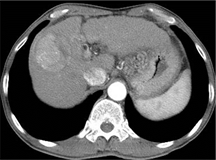

造影剤を用いたCT検査はすでに我が国に広く普及し、様々な疾患の画像診断に役立っています。しかし、肝臓や腎臓などの臓器や癌などの腫瘍性病変の血流量を数値として測定することはできませんでした。本研究では新たなCTの撮影法と解析法を用いることで、腹部実質臓器や疾患の血流量を測定し、より確かな画像診断技術を開発することを目的としています。

結果の一部は論文として発表されています。